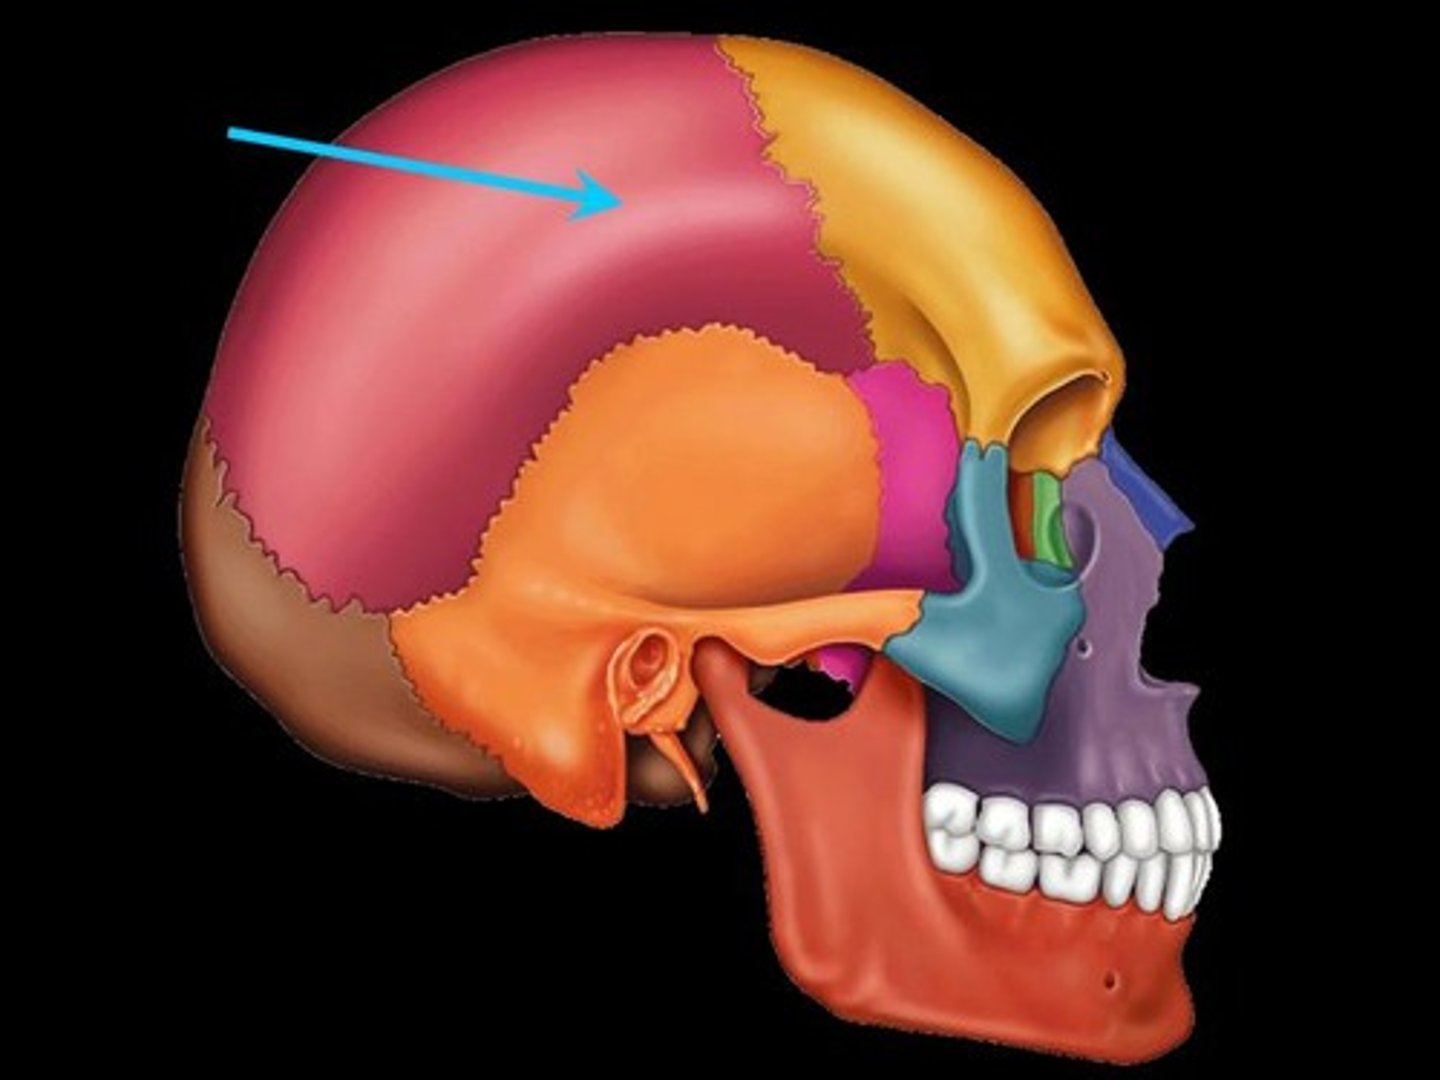

coronal suture

sagittal suture

squamosal suture

lambdoidal suture

bregma

lambda

pterion

asterion

frontal bone

parietal bone

sphenoid bone

occipital bone

temporal bone